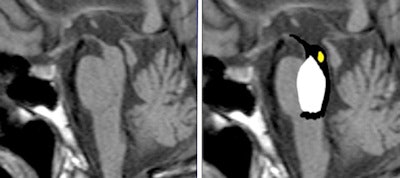

The "penguin sign" may signal progressive supranuclear palsy. In this image, atrophy of the tectum, particularly the superior colliculus, can be seen. Image courtesy of Dr. Laughlin Dawes, Sir Charles Gairdner Hospital, Perth, Australia.An example of these useful signs is the "penguin" seen in an MRI of the brain. More than amusing, the penguin is an interesting radiological sign seen in patients with progressive supranuclear palsy (PSP), noted Arora. It refers to atrophy of the midbrain tegmentum, with a relatively preserved pons on midsagittal T1-weighted images. The "penguin sign" can be helpful in distinguishing progressive supranuclear palsy from multisystem atrophy and Parkinson's disease.